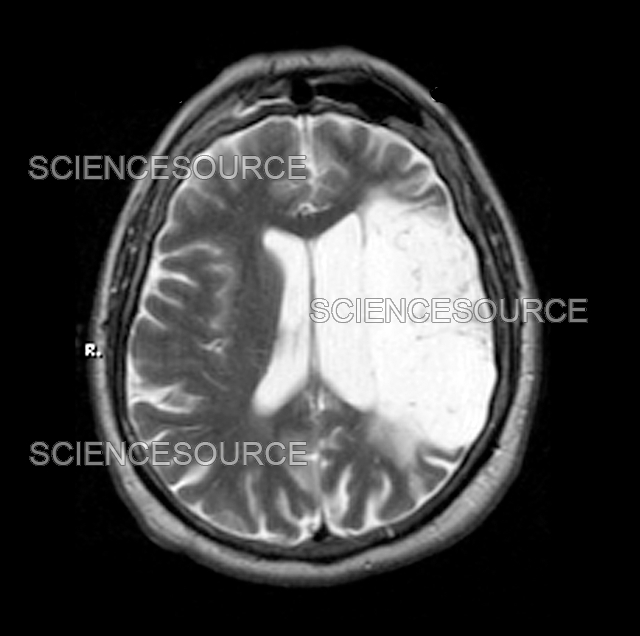

Old Stroke, MRI Stock Image C004/7487 Science Photo Library Old Stroke Radiology The second part, appearing in the november/december 2021 issue. Use of various mr imaging sequences in dating ischemic stroke is discussed, with a brief review of the current and most widely accepted guidelines for thrombolytic and. Hyperacute (less than 12 hours), acute (12 to 24 hours), subacute (24 hours to 5 days), and old (within weeks after stroke). The key. Old Stroke Radiology.

Old Stroke, MRI Stock Image C004/7485 Science Photo Library Old Stroke Radiology Ncct findings in ischemic stroke depend on the age of infarction: Hyperacute (less than 12 hours), acute (12 to 24 hours), subacute (24 hours to 5 days), and old (within weeks after stroke). Use of various mr imaging sequences in dating ischemic stroke is discussed, with a brief review of the current and most widely accepted guidelines for thrombolytic and.. Old Stroke Radiology.

Photograph Old Stroke, MRI Science Source Images Old Stroke Radiology Exclude hemorrhage differentiate between irreversibly affected brain tissue and. Hyperacute (less than 12 hours), acute (12 to 24 hours), subacute (24 hours to 5 days), and old (within weeks after stroke). Unenhanced ct can be performed quickly, can help identify early signs of stroke, and can help rule out hemorrhage. The goal of imaging in a patient with acute stroke. Old Stroke Radiology.